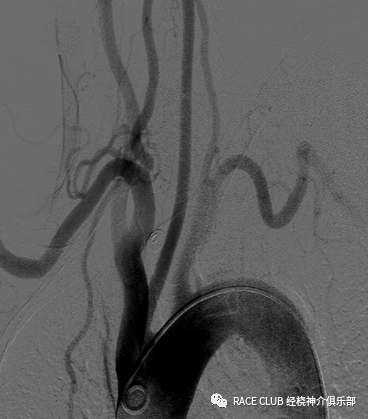

弓上造影(股动脉入路)

接三通、y阀,排气 •接上单弯导管或西蒙导管排水

•透视下推床,露出升主动脉

•进泥鳅导丝,将猪尾导管头端拉直,一起退出

•将单弯导管或西蒙导管头端送入血管鞘内,泥鳅导丝浸水后从y阀送入,透视下将导管导入,分别进入右锁骨下动脉、双侧颈总动脉(颈内动脉)、左锁骨下动脉造影